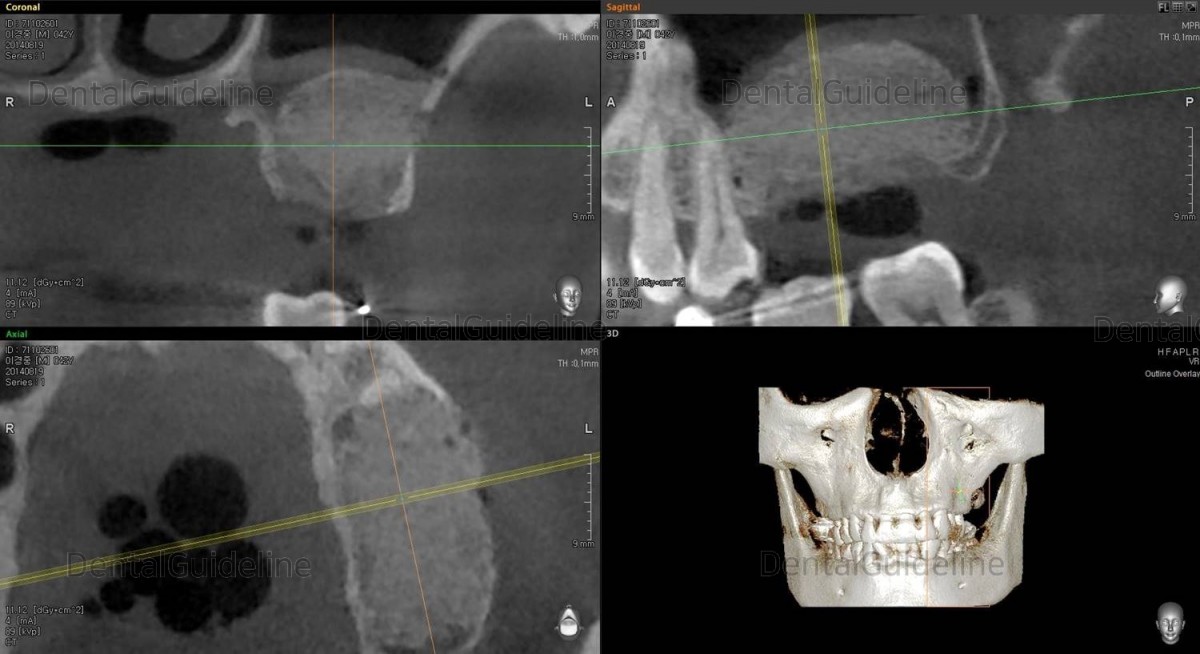

3. 2 months after tooth extraction. The tooth extraction site and the inside of the maxillary sinus healed well.